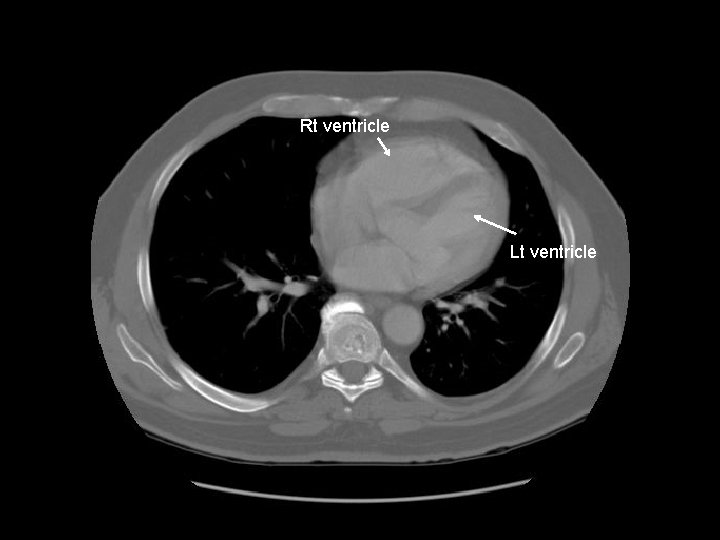

Rt ventricle

Rt ventricle Lt ventricle

Interventricular septum